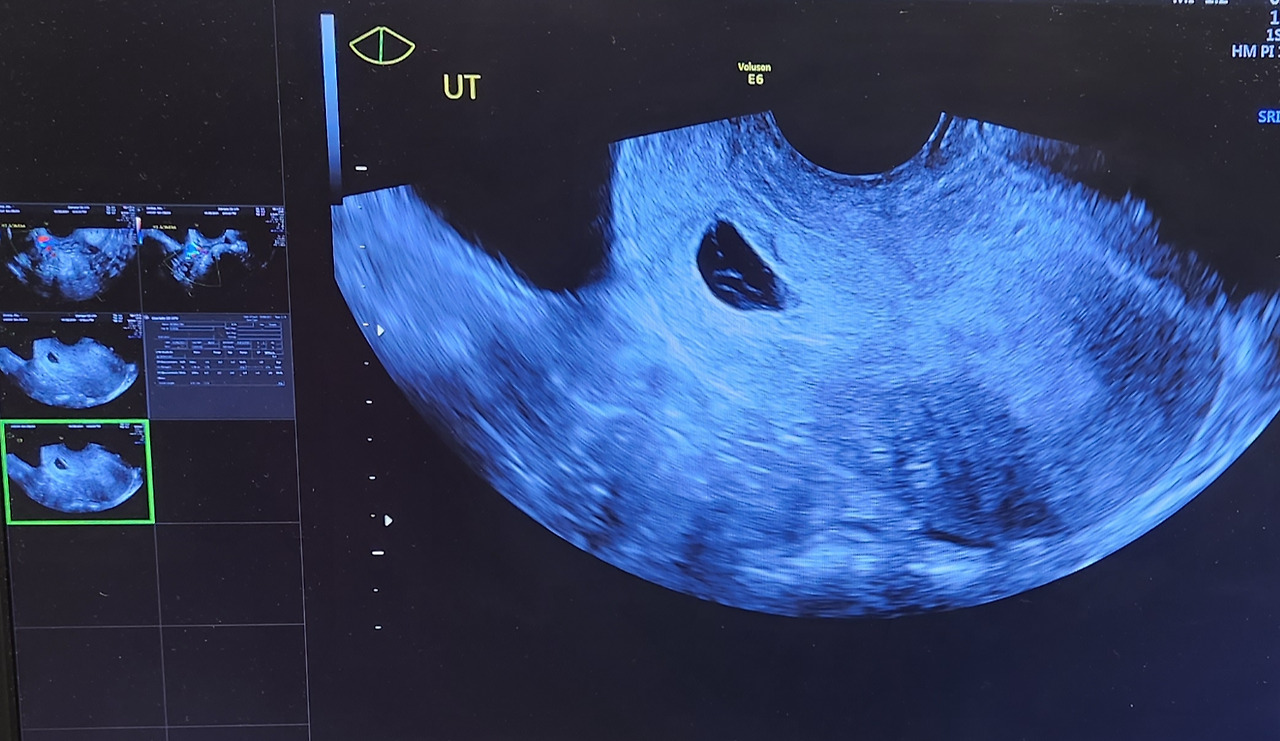

초음파 검사를 받았다.

아직 안에 아이 집이 남아있고, 깨끗하게 다 나오게 하려면 약을 먹어야 한다는 것.

20230308_170913.jpg 유산 진단을 받고, 아기집이 비어있는 걸 다시 확인